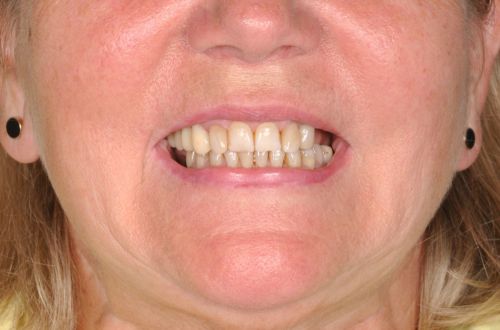

Wykonana praca protetyczna:

- licówki pełnoceramiczne na zębach górnych przednich

- korony pełnoceramiczne na zębach własnych w łuku górnym i dolnym

- korony na implanatch